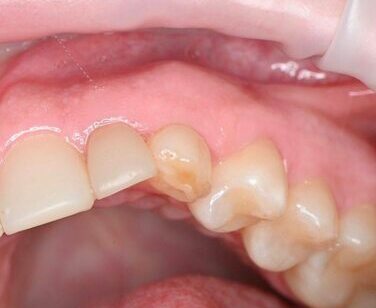

Выполнено планирование имплантация, до операции изготовлена временная коронка. В день операции удаление 63, имплантация по навигации, установка временной коронки.

Клинический случай имплантации с премиальной системой PALTOP

Одномоментная имплантация

Коронка изготовлена до операции и зафиксирована сразу после установки имплантата.